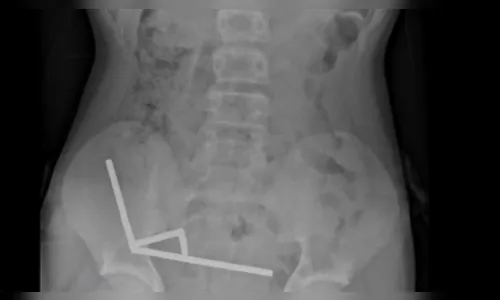

Os exames mostraram que os ímãs haviam se agrupado em quatro correntes na parte inferior direita do abdômen, conectando diferentes seções do intestino por meio da força magnética. Essa interação causou necrose por pressão — morte do tecido intestinal provocada pela compressão —, além de risco de perfuração e infecção grave.